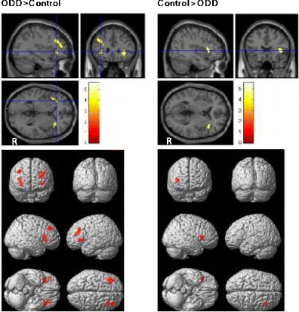

Functional Magnetic Resonance Imaging (fMRI) of inhibitory control has only been investigated in patients with attention deficit hyperactivity disorder (ADHD) and conduct disorder (CD). The objective of this study was to investigate the differences of functional areas associated with inhibitory control between boys with pure oppositional defiant disorder (ODD) and controls during a response inhibition task using functional magnetic resonance imaging (fMRI). Eleven boys with pure ODD and ten control boys, aged 10 to 12, performed a GoStop response inhibition task in this study. The task has a series of “go” trials to establish a pre-potent response tendency and a number of “stop” trials to test subjects’ ability to withhold their responses. During the GoStop task, greater activation in the dorsolateral parts of the bilateral inferior frontal gyrus, left middle frontal gyrus (lMFG) and right superior frontal gyrus (rSFG) activation was seen in the ODD boys. Additionally, reduced activation in regions of the right inferior frontal gyrus (rIFG) was seen in the ODD boys in comparison with the control group. The results may suggest that the higher activation in areas adjacent to the rIFG could be the cause of reduced activation in the rIFG; although this is speculative and requires additional supporting evidence. The findings further suggest that ODD is a less pronounced functional disorder compared to ADHD and CD.

Fig. 4